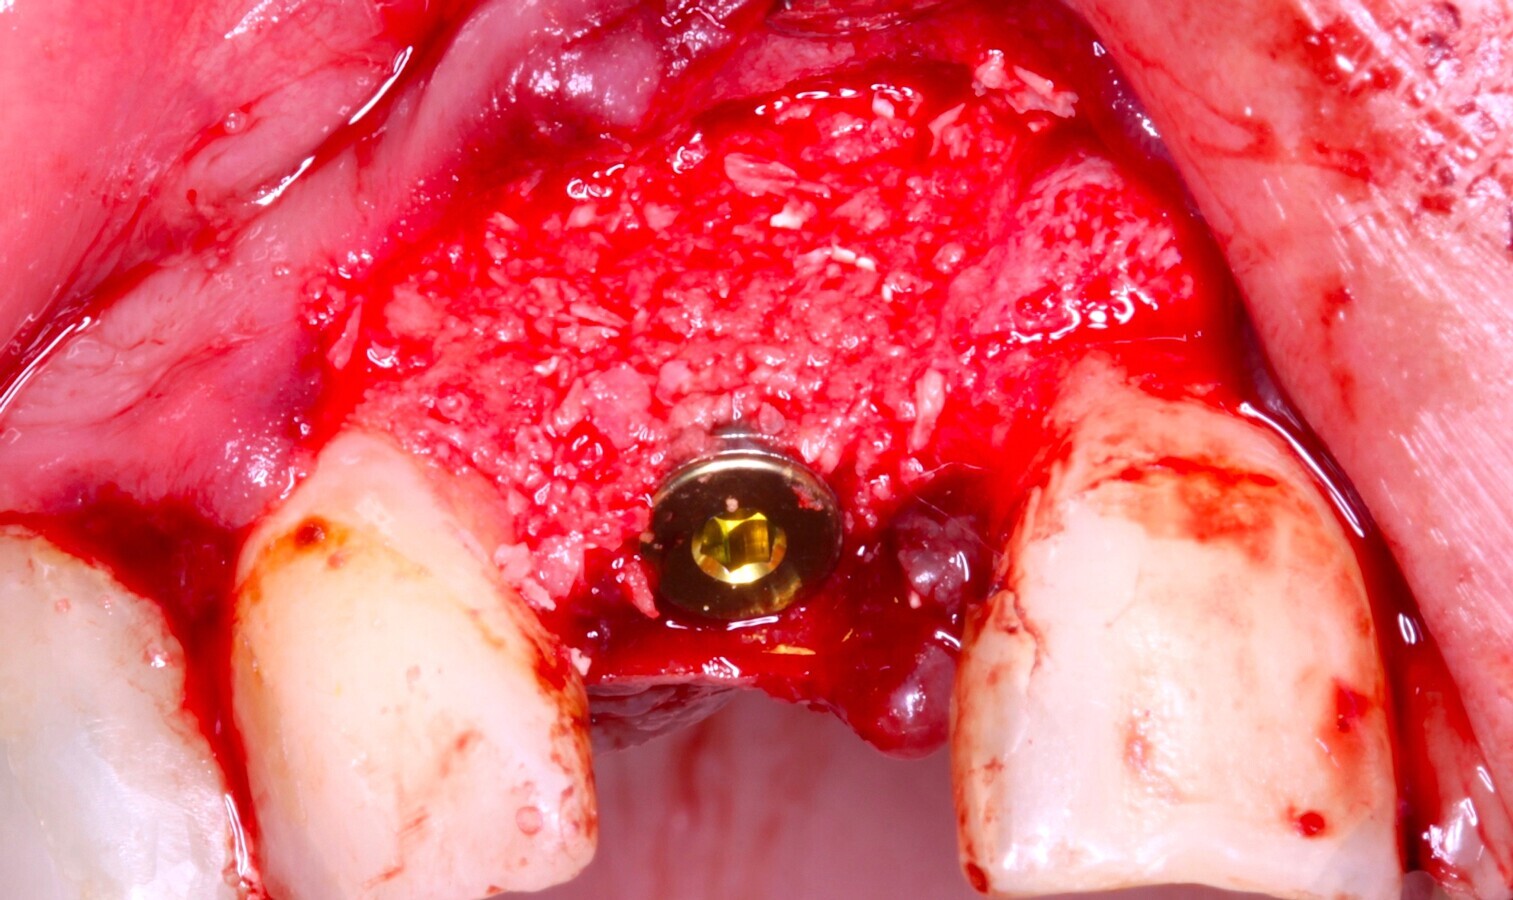

ELEVACION CON COLOCACION SIMULTANEA DEL IMPLANTE

(Clasificación de Jensen & Jensen, Clase B)

- 1ª Opción: Relleno de la cavidad sinusal con el material de injerto y posterior preparación del lecho y colocación de implantes dentales.

- 2ª Opción: Preparación del lecho y colocación de implantes dentales y posterior relleno de la cavidad sinusal con material de injerto.

Fig. 24 Figura 24

7. Reposición del colgajo mucoperióstico, en caso necesario liberación de periostio para garantizar un colgajo sin tensión, cierre primario del lecho10.

8. Sutura de los colgajos con puntos simples y colchoneros horizontales con sutura 4/1011,12.